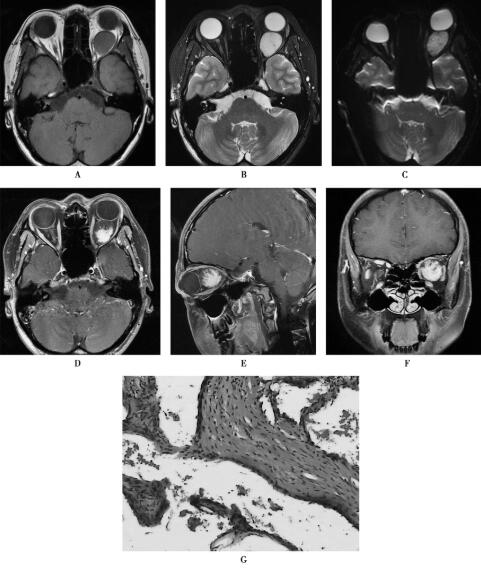

应用3.0T超导型MRI扫描仪(HDx,GE),8通道头线圈,获取SE序列体轴横断位T1WI(TR/TE=500ms/13.27ms),3mm层厚,1mm间隔,512×512矩阵,180mm视野,FSE加脂肪抑制横断和冠状位T2WI[TR/TE=(3660~6600ms)/(48~103.25ms)],3mm层厚,1mm间隔,512×512矩阵,180mm视野。扩散加权成像(DWI):b=1000s/mm2,TR/TE=5575ms/77ms,180mm视野,3mm层厚,1mm间隔。应用钆喷酸葡胺(剂量0.1mmol/kg体重)进行增强扫描,注射流率2.5ml/s,获取横断位、冠状位和矢状位T1WI(图1)。

图1左眼眶海绵状血管瘤

1.眼眶海绵状血管瘤球后有类圆形肿块影,信号均匀,T1WI低信号、T2WI和DWI呈高信号,增强扫描肿块表现为“渐进性强化”,邻近眼外肌和视神经受压移位,眶尖和眶周骨质未见异常改变。

左眼眶海绵状血管瘤。HE染色(×40倍),镜下可见排列紊乱的大小不一的血管团(图1G)。

眼眶海绵状血管瘤是成人眶内最常见良性肿瘤,好发于青中年女性,常单侧发病,生长缓慢,视力一般不受影响。渐进性轴性眼球突出是常见临床表现。海绵状血管瘤由大小不等血管腔构成,内部血液流动缓慢。本肿瘤在T1W I上呈等或略低信号,T2W I上呈高信号。多回波脉冲序列上伴随TE值升高,海绵状血管瘤的信号强度亦升高,此征象和增强扫描病灶渐进性强化为血管瘤的特征性改变,据此MRI可作出眼眶海绵状血管瘤的定位和定性诊断。本病一般不累及眶尖,故眶尖正常脂肪仍然存在。